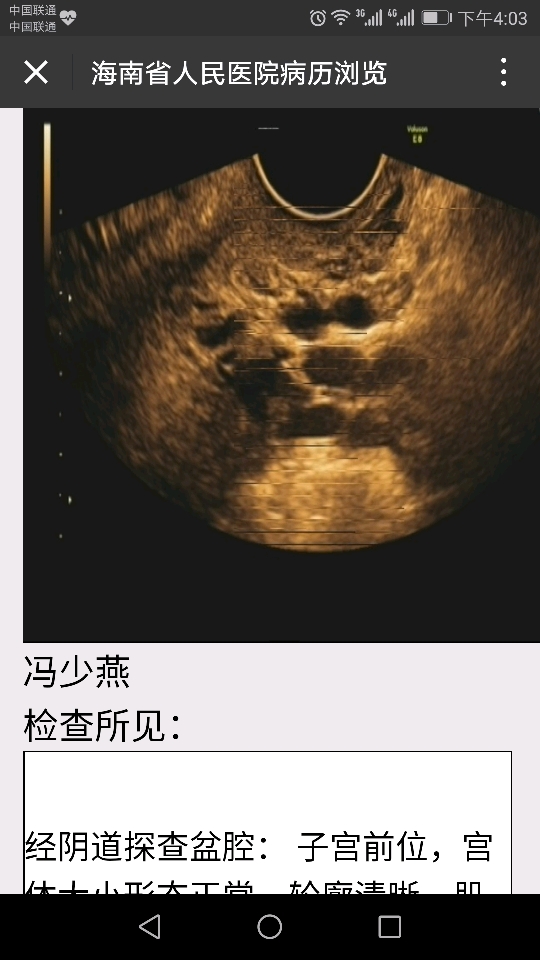

月经每个月都有来六七天但是量很少很少,第三天就基本没有但就是拖到六七天才干净,大小便隔天一次,自己测过一个月没有排卵日,检查六项孕酮低,想怀孕要怎么治疗

Screenshot_20170418-160323_temp_1492503034994.png

Screenshot_20170418-155905.png

Screenshot_20170418-155833.png

IMG_20170418_155058_temp_1492503035225.jpg